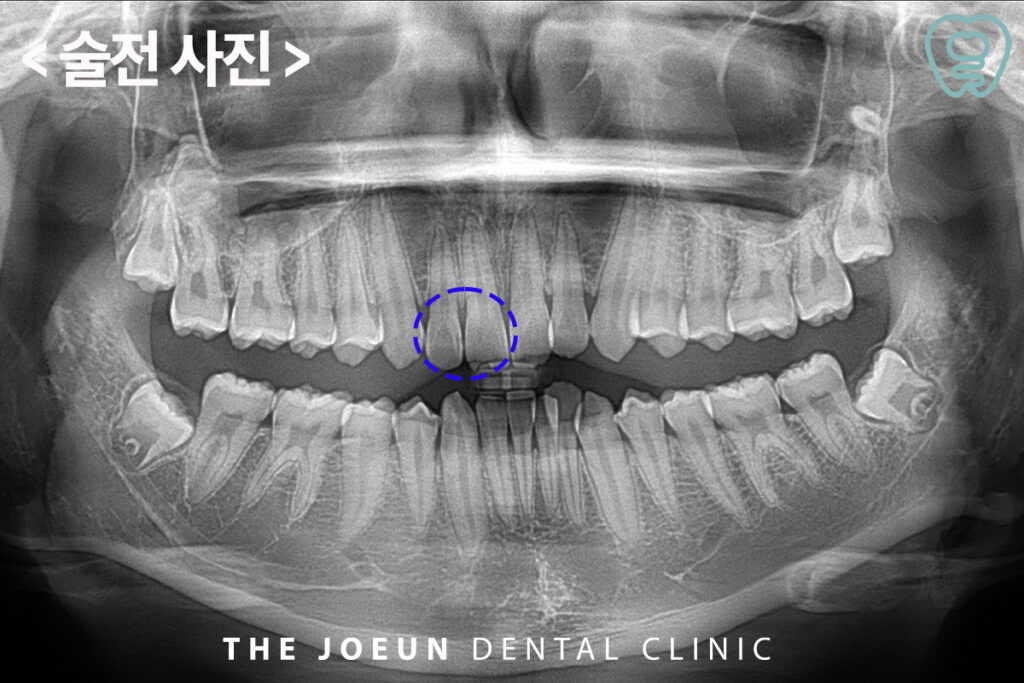

오늘은 외부 충격으로 인해 깨진 앞니와 충치가 생긴 옆의 치아까지 레진으로 수복하신 환.자분을 소개해 드릴까 합니다. 환.자분께서는 앞니가 부딪혀서 깨지셨다며 치료를 위해 내원해 주셨는데요.

앞니는 끝부분이 깨진 상태였고, 옆의 치아에는 충치가 있는 것처럼 보여 x-ray 사진을 촬영해 보았더니 근심 쪽의 우식이 관찰되었습니다.

깨진 앞니의 부위가 많이 크지 않아 옆의 치아의 충치까지 레진으로 수복하기로 하였습니다.